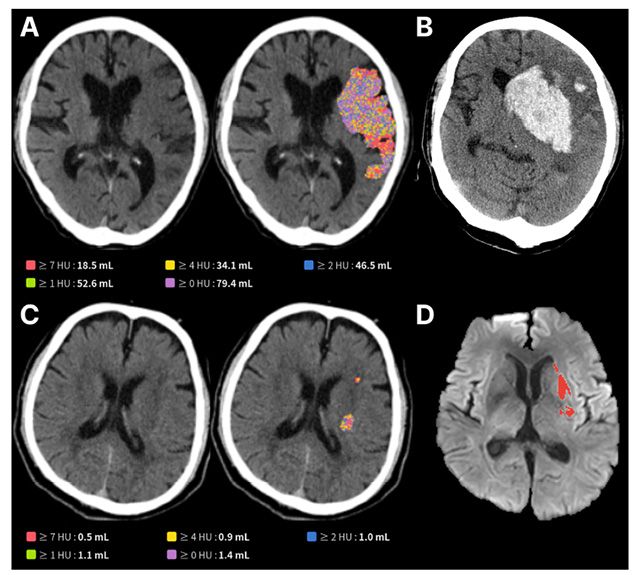

- ▲ A. JLK-CTI 예측 뇌경색 범위가 넓은 환자, B. 시술 이후 뇌출혈 발생, C. 예측 뇌경색 범위가 넓지 않은 환자, D. 시술 이후 작은 뇌경색으로 좋은 예후 /이미지 제공=제이엘케이

제이엘케이의 AI 모델은 NCCT와 확산강조영상(DWI) 데이터를 학습해 미세한 뇌 손상 영역을 자동 검출하고 부피를 정량화하도록 설계됐다. 연구팀은 국내 6개 뇌졸중 센터에서 확보한 603명 환자 데이터를 분석해 임상적 유효성을 검증했다. 그 결과, 손상 부피가 50mL를 초과할 때 3개월 후 회복 가능성이 17.3%로, 50mL 이하 환자(54.2%)보다 현저히 낮았다. 또 손상 부피가 큰 환자일수록 뇌출혈 등 합병증 발생 위험도 더 크게 나타났다. 이는 응급실 기본 영상만으로도 장기 예후를 예측할 수 있음을 보여주는 근거를 제시했다.